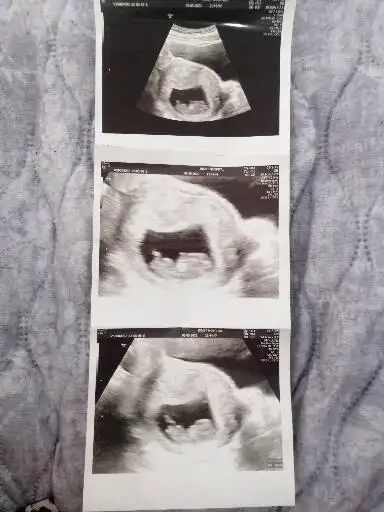

Merhaba Pasha22 Pasha22 acaba bana da yorum yapabilir misiniz? Merakla bekliyorum cinsiyeti.

Ilk foto 13+4

2.foto 11+5

3.foto 6+3

Hepsi karından.